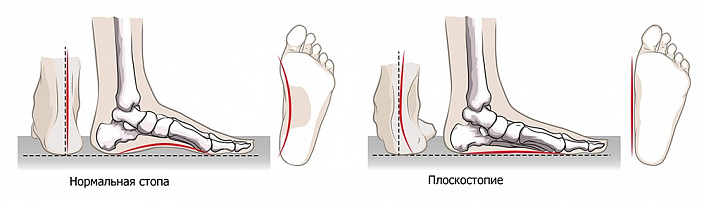

Связки и мышцы

При беге у взрослого человека нагрузка на стопу возрастает в четырёхкратном размере от его веса, поэтому сухожилия стоп очень прочные. Плотно оплетены сухожилиями суставы лодыжки, обеспечивая приём веса, приходящегося на таранную кость, попутно они защищают сустав от неверного движения. Связки, расположенные между плюсневыми костями и идущие от пятки к плюсне, обеспечивают амортизацию обоих сводов стопы. Когда они ослаблены, развивается плоскостопие.

Заболевания стоп, как правило, сопряжены с массой дополнительных проблем. Постановка стопы влияет на осанку, положение костей конечностей и таза. У людей с деформированными стопами наблюдается асимметрия всего тела, часто встречаются искривления позвоночника. Среди наиболее часто встречающихся патологий стопы — это её деформация. Она может быть как следствием травм, так и врождённая. Самая известная, конечно, это плоскостопие.

Плоскостопие может быть продольным, когда ослаблена подошвенная связка и мышца, или поперечным, когда плюсневая кость большого пальца отклоняется из-за растяжения межплюсневых связок. В любом случае стопа теряет свои амортизационные свойства.

Проверяют ногу на продольное плоскостопие с помощью отпечатка стопы: если есть отпечаток с внутренней стороны стопы, то стопа плоская, если нет — то свод приподнят и плоскостопия нет. При такой деформации стопы ноги быстро устают, в плюснах возникают боли, женщины не могут ходить на высоких каблуках. Развивается заболевание в 7–9 лет, в период роста костей, т. е. до 18 лет оно может усугубиться. С возрастом эластичность связок и мышц снижается, так что нагрузка на стопу возрастает ещё больше. У взрослых людей плоскостопие чаще встречается у женщин из-за неправильной обуви, при беременности и гормональных изменениях, а у мужчин — от избыточного веса. Все люди с большим весом рано или поздно начинают страдать от плоскостопия.

На протяжении жизни человека важно отслеживать состояние стоп, первый раз обратить внимание на стопу следует в раннем детстве, когда человек начинает ходить. Если есть врождённые патологии, не замеченные сразу, то здесь они проявятся, так как появится нагрузка на стопы. Следующий этап — поступление в школу: снова возрастает нагрузка на ноги. Далее — подростковый период, когда кости растут наиболее быстро. В возрасте 30 лет происходят изменения вследствие неправильного образа жизни и ношения плохой обуви. И с возрастом, конечно, кости, связки и кровоток начинают слабеть, что может привести к усугублению болезни. Лечат плоскостопие гимнастикой, ортопедическими стельками, специальной обувью и оперативно. Если у человека врождённые гиперэластичные связки, то плоскостопие для него не новость, но тренировка мышц может выправить ситуацию.